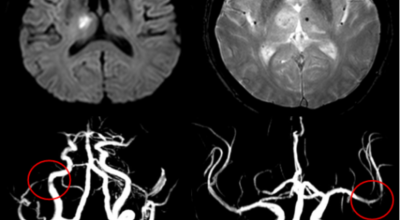

뇌경색 치료방법

뇌경색 초기증상이 나타나면 가장 중요한 것은 빠른 인지와 빠른 치료예요. 뇌세포는 뇌혈관이 막히는 순간부터 빠르게 손상이 진행이 되고 재생은 어렵기 때문입니다. 뇌와 연관된 질병은 골든타임을 놓치지 않는 것이 제일 중요해요.

큰 뇌혈관이 막힌 경우라면 발생한지 4시간 반 안에 정맥 내로 혈전 용해제를 투여해 막힌 혈관을 뚫어주게 되고 6시간 이내라면 직접 동맥 내 시술을 통해 혈관을 막은 혈전을 직접 제거하는 혈전제거술을 시행하게 되는데요.